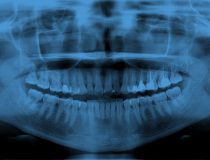

Dowiedz się np: czym jest pantomogram?

Najczęstszym wskazaniem do wykonania badania pantomograficznego u dziecka jest ocena zębów wyrzynających się, opóźnionych i zatrzymanych, a także obecności zawiązków zębowych, zębów dodatkowych i nadliczbowych, ocena wieku zębowego, ocena patologii tkanki kostnej oraz urazów

więcej >>Jaka jest dawka promieniowania przy wykonaniu pantomogramu?